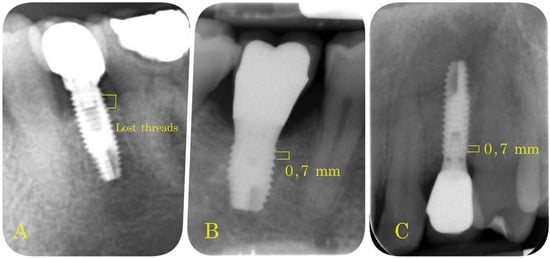

- Marginal Bone Loss (MBL): periapical intraoral radiographs were used to evaluate bone loss around the implants (Sirona Heliodent with 1 mm aluminum filter). A Rinn Endoray® plate holder (Markham, ON, Canada) was used to maintain the same object focus distance for all patients, and to avoid focus distance variations that could lead to inaccurate results. The distance between the bone crest and the implant shoulder on both mesial and distal aspects was measured from periapical radiographs by the same operator in all cases. These measurements were expressed by the number of implant threads lost (Figure 4).